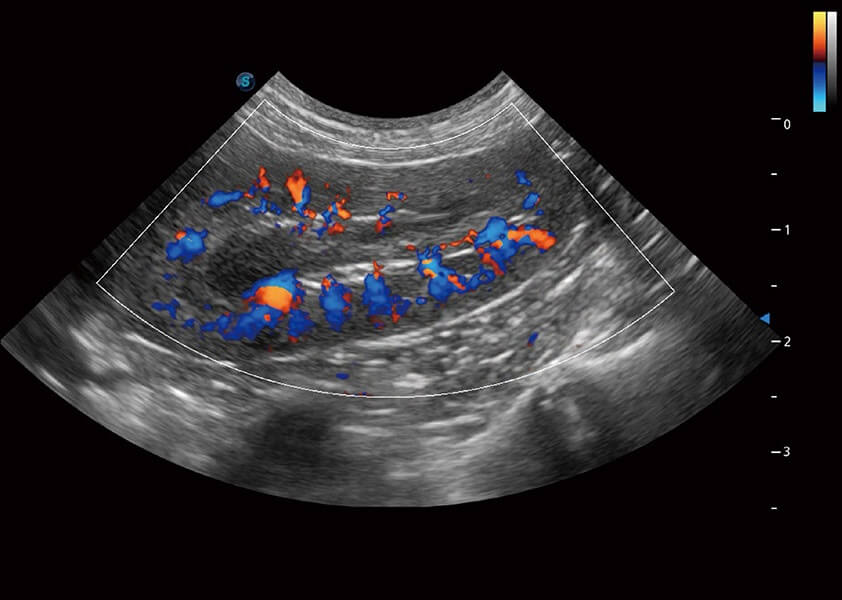

优异的基础图像

(犬)肾脏血流